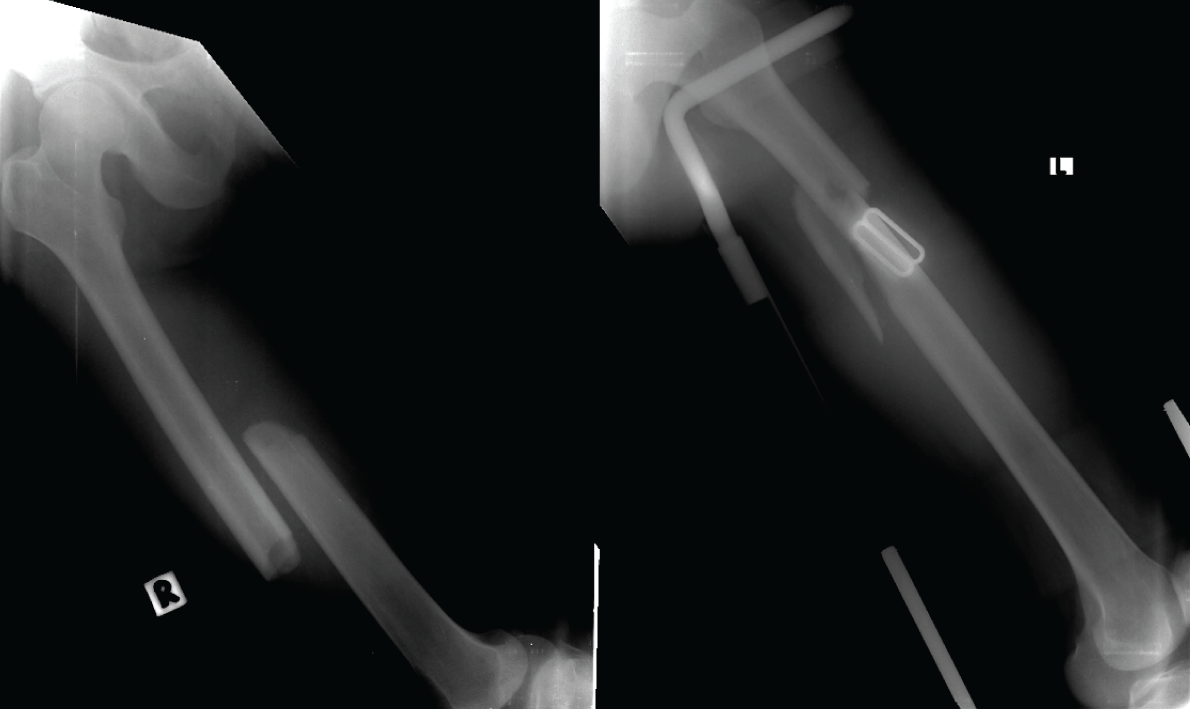

On the orthopedics side, he was put on bilateral high tibial pin skeletal traction for fractures shaft femur (Figure 2) while waiting for definitive management later once the general condition becomes more stable. Neurosurgery team was decided to continue conservative management for the head injury.

Figure 2: Bilateral midshaft femur fracture.